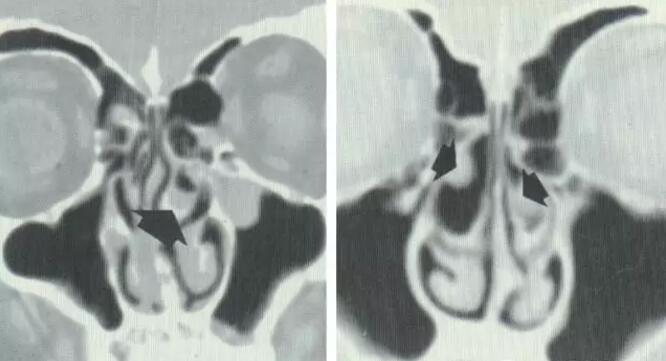

钩突解剖变异:钩突内偏、肥大

导致中鼻道狭窄,引流障碍

钩突的解剖变异:钩突外偏

钩突外偏引起筛漏斗狭窄,上颌窦引流不畅